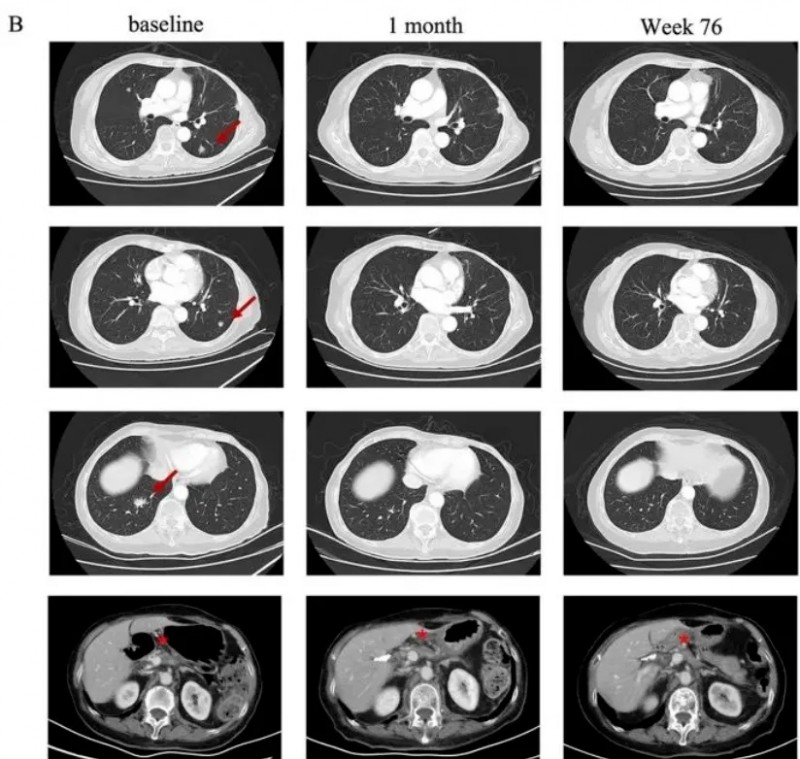

细胞免疫疗法治疗胰腺癌效果好吗,来看看这三个成功案例免疫细胞疗法"精准打击"胰腺癌CAR-T治疗转移性胰腺癌,达到完全缓解世界知名期刊《新英格兰医学杂志》,报道了1例75岁的转移性胰腺癌患者,经CT041细胞治疗后,靶病灶和转移灶明显缩小的案例。CT041是一种自体CAR-T细胞候选产品,先后获得美国FDA授予的再生医学先进疗法(RMAT)资格、我国NMPA